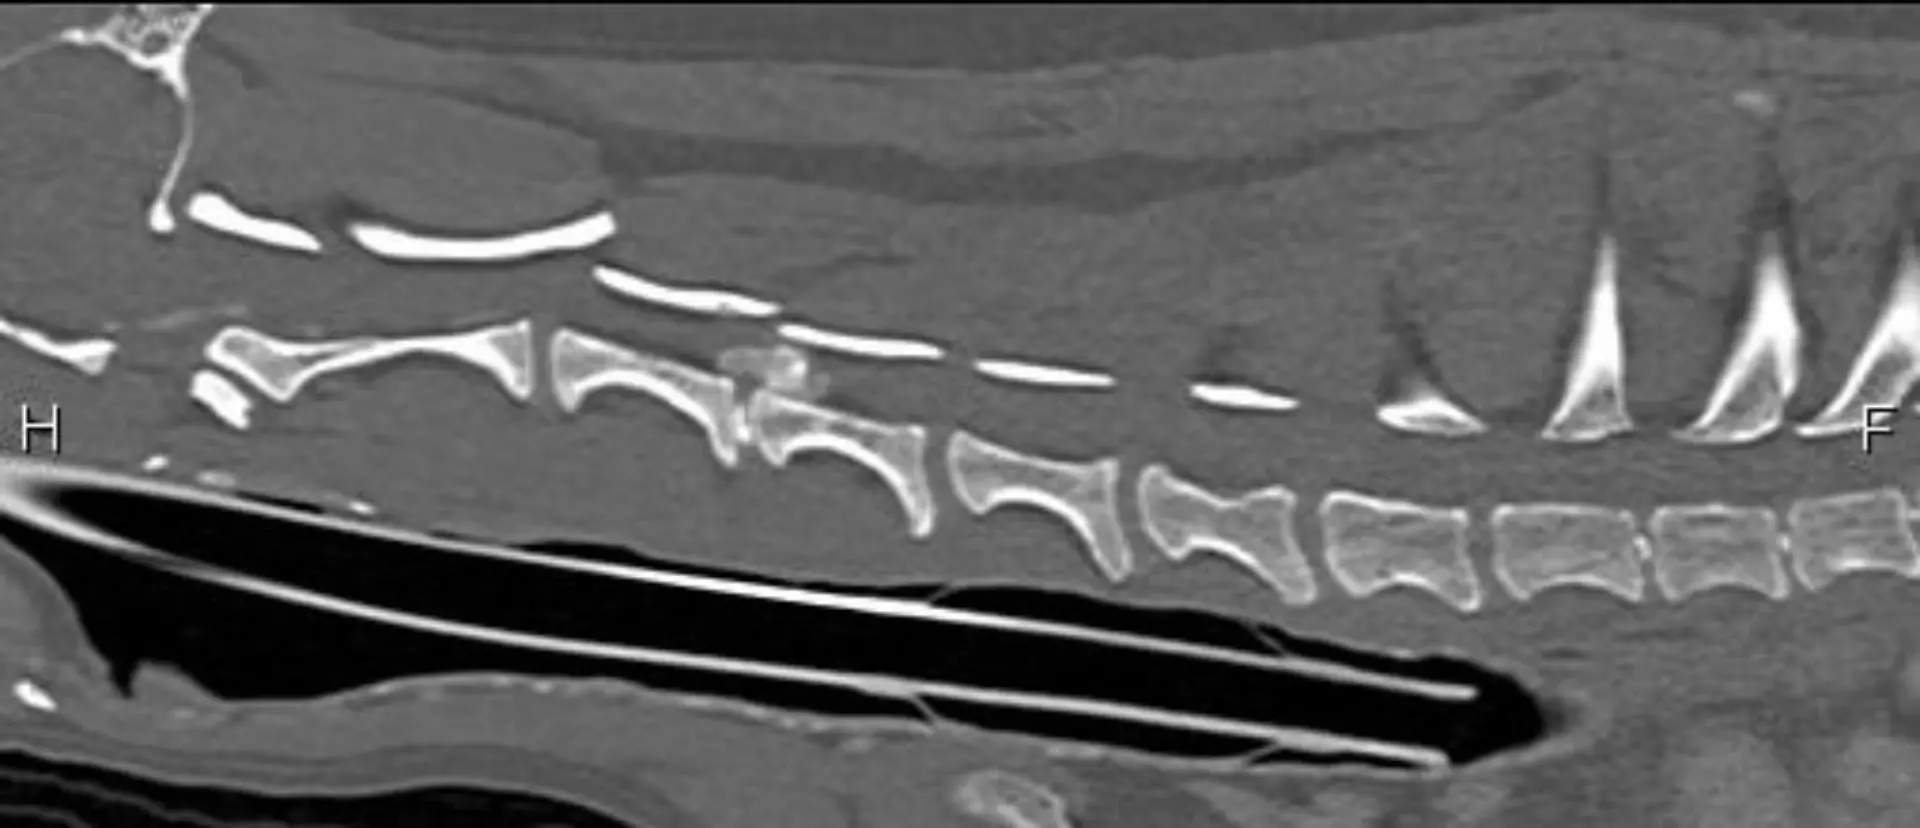

The neurology center at Veterinary Specialists of Greater New Orleans is led by our board-certified veterinary surgeons. Our neurology center is uniquely equipped to treat conditions of the nervous system, spine, and peripheral muscles and nerves. Neurological conditions may often be treated medically, but when those options are not successful, our experienced surgical team will use the most advanced surgical techniques along with our state-of-the-art veterinary tools and equipment. Prior to any neurological procedure, our board-certified veterinarians will perform a complete examination of the pet which will include a physical exam, diagnostic analysis, and digital x-ray or CT scan as necessary. Our doctors will determine the appropriate course of action for your pet, and fully discuss the treatment plan with you and your veterinarian.

- Ruptured intervertebral discs (IVDD)

- Spinal tumors

- Spinal Fractures